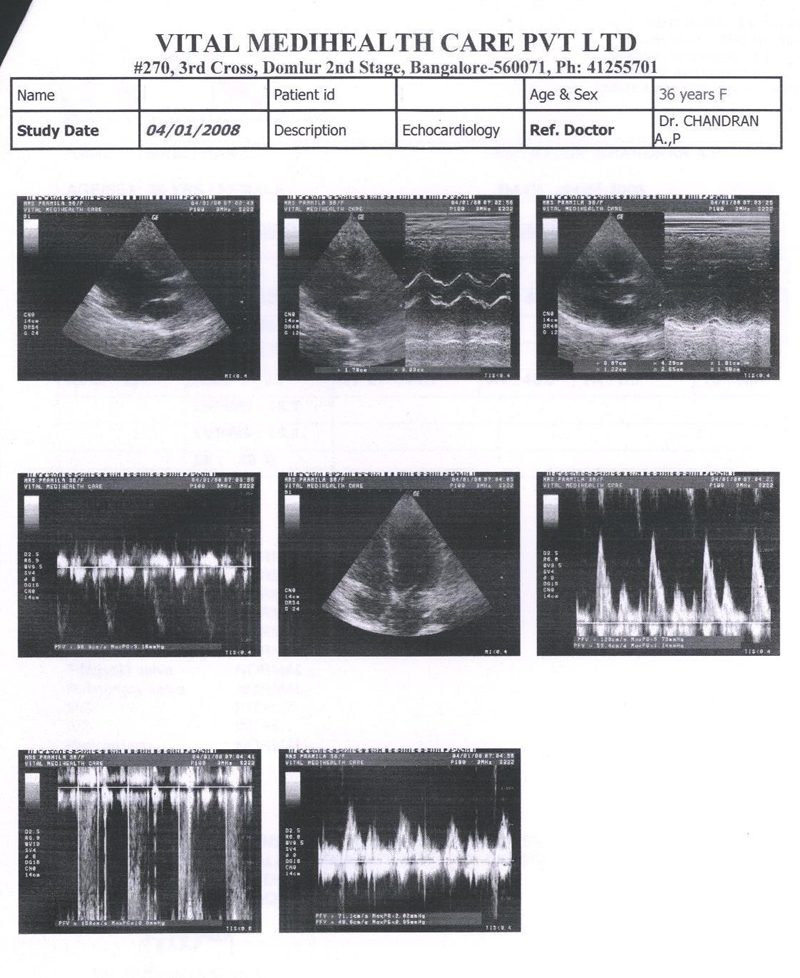

Echocardiography was done and shows that the valves are much better, the abnormal murmur heard using stethoscope have almost disappeared. Echocardiography report is shown in FIG3. Placebo continued

FIG 3:- Echocardiography report of 27th Nov. 2007